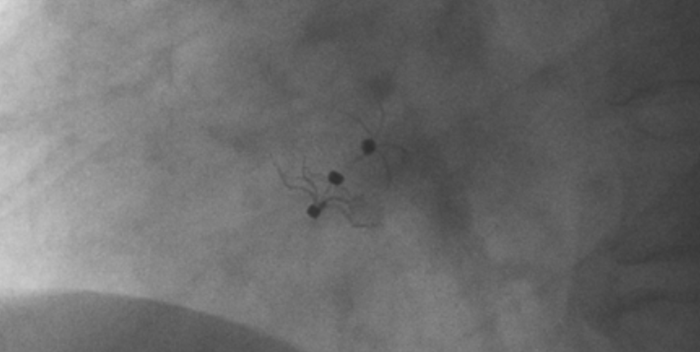

影像顯示試驗(yàn)器械適應(yīng)性貼合于房間隔兩側(cè)且穩(wěn)定

術(shù)中造影顯示患者為PFO且長隧道型,目前市場上已商業(yè)化的PFO封堵器難以滿足該患者解剖結(jié)構(gòu)封堵需求。迪創(chuàng)醫(yī)療自主研發(fā)的OmniSeal PFO封堵器自適應(yīng)性雙盤貼合設(shè)計(jì)能廣泛適應(yīng)不同PFO隧道長度的解剖結(jié)構(gòu)和形態(tài),其雙盤外包覆式阻流和隧道內(nèi)填充阻流相結(jié)合的雙重阻流設(shè)計(jì),可為此患者實(shí)現(xiàn)有效封堵。與此同時,OmniSeal首創(chuàng)的完全可穿刺式設(shè)計(jì),也為此患者最大程度地保留了房間隔區(qū)域穿刺通道,以實(shí)現(xiàn)全兼容未來可能的左心系統(tǒng)二次介入術(shù)。術(shù)終造影和心臟超聲顯示封堵完全、效果良好。作為OmniSeal的首例臨床應(yīng)用,本次手術(shù)的順利完成和優(yōu)異效果充分體現(xiàn)了產(chǎn)品的設(shè)計(jì)創(chuàng)新優(yōu)勢。

迪創(chuàng)醫(yī)療自主研發(fā)的OmniSeal PFO封堵器系統(tǒng)具有多項(xiàng)創(chuàng)新設(shè)計(jì)和技術(shù)優(yōu)勢,并且對于目前市場商業(yè)化產(chǎn)品的多個臨床痛點(diǎn)問題,如難以開展左心系統(tǒng)二次微創(chuàng)介入手術(shù)、術(shù)后新發(fā)心房顫動、殘余分流、血栓形成等器械相關(guān)的限制和并發(fā)癥等,提供了針對性的解決方案。OmniSeal PFO封堵器系統(tǒng)獨(dú)創(chuàng)的完全可穿刺式設(shè)計(jì),能實(shí)現(xiàn)全兼容左心系統(tǒng)二次介入術(shù)。其較高的適應(yīng)性使得產(chǎn)品可以適應(yīng)不同卵圓孔未閉解剖學(xué)結(jié)構(gòu)和形態(tài),并減少對房間隔的刺激, 降低術(shù)后心律失常事件。同時,雙盤外包覆式阻流和隧道內(nèi)填充阻流相結(jié)合的創(chuàng)新結(jié)構(gòu)在確保有效封堵的情況下,減少殘余分流,降低血栓形成。